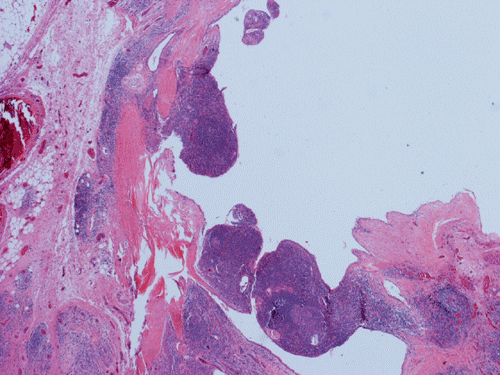

Histopathology: The lesion is encapulated cystic structure with the wall lined by nodules of lymphoid tissue (Panel A  and B) that are devoid of any evidence of hematopoiecic malignancy. Within this lymphoid tissue are small pink islands (Arrow in Panel C) and on higher magnification (Panel D) these islands are squamous cell nests. These islands are Hassell corpuscles and the lymphoid tissue is in fact thymic tissue. The cyst appears to have sustained repeated hemorrages. Both recent hemorrhage (Panel E) and cholesterol clefts consistent with resolved hemorrhage (Panel F) are present.